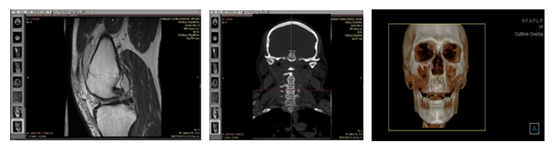

Computational Bioinformatics is a novel tool that can be applied in the study of the behaviour presented by the different levels of organization of living matter (cells, tissues and organs), under the effects of stimuli and external agents, such as burdens mechanical, which influence the behaviour of cellular metabolism.1 Through the generation of anatomical biomodels, is interested in solving biological problems in a multidisciplinary and interdisciplinary way. It uses computational tools for the rapid organization and analysis of biological data. Which, in addition to making use of databases, also uses algorithmic processes and computer programs to perform high-speed evaluations and analyses to study the ethiology and the natural history of the disease, which make it possible to establish diagnoses, treatment plans, prognosis and until the prevention of some disease. Nowadays, digital imaging is widely used as part of diagnostic means in practically all medical areas. However, the programs or viewers that offer the radiological services only allow a very reduced vision to explore the anatomical structures. However, if these diagnostic means are used in conjunction with Computational Bioinformatics, the images obtained from them allow a visualization and manipulation that offers better results (Figure 1).

Figure 1 Three-dimensional imaging.

With the images obtained from the imaging studies, it is possible to generate biomodels that allow a better exploration of the anatomical structures to be treated, observe them with greater precision and even be able to perform numerical analyzes that also provide a better diagnosis, a planning of the treatment or treatments that can be performed on the patient, which will result in better prognoses and treatments with a higher success rate. The biomodels allow a better understanding of the biomechanical mechanisms of living systems, through high precision images obtained from Computed Tomography, TC Conebeam,2 Magnetic Resonances and CAD programs. These models have a morphology with a high degree of accuracy or bio-fidelity. Which, in turn, has allowed establishing the mechanical properties of each of the tissues that make them.3 This allows obtaining results with greater shutdown to the biological function (Figure 1), as well as better diagnoses without invasive techniques (Figure 2).